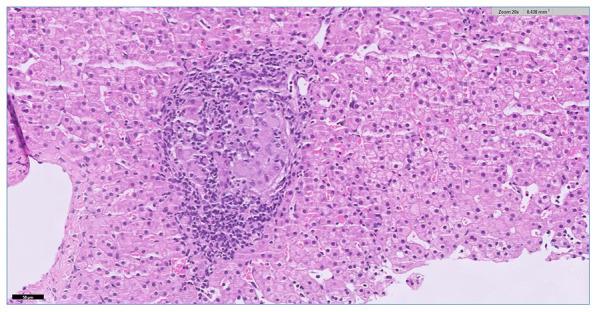

Interleukin-2 receptor alpha () defect (OMIM- # 606367) is an immune disease where affected patients are vulnerable to developing recurrent microbial infections in addition to lymphadenopathy and dermatological manifestations. This condition is known to be caused by pathogenic variants in the gene, which are inherited in an autosomal recessive fashion. In this case report, we present a patient with defect from Saudi Arabia who presented with chronic diarrhea, poor weight gain, mild villous atrophy, malnutrition, hepatomegaly, nonspecific inflammation, and an eczematous skin rash. His genetic analysis revealed a novel, homozygous, and likely pathogenic variant, that is, c.504 C>A (Cys168Ter), located in the exon 4of the gene, which was inherited from his parents in an autosomal recessive mode of inheritance. This variant produces a 272-amino-acid shorter protein chain, which most likely becomes degraded in the cytosol. Thus, we assume that the c.504 C>A is a null allele that abolishes the synthesis of , malforms the IL-2 receptor complex, and eventually causes immunodeficiency manifestations. To our knowledge, this is the first time a person with defect has shown signs of granulomatous hepatitis on a liver biopsy.

白细胞介素-2受体α(IL-2Rα)缺陷(OMIM编号:606367)是一种免疫疾病,患病患者除了会出现淋巴结病和皮肤病表现外,还容易反复发生微生物感染。已知这种病症是由IL-2Rα基因的致病变异引起的,这些变异以常染色体隐性方式遗传。在本病例报告中,我们介绍了一名来自沙特阿拉伯的患有IL-2Rα缺陷的患者,该患者出现慢性腹泻、体重增加缓慢、轻度绒毛萎缩、营养不良、肝肿大、非特异性炎症和湿疹样皮疹。他的基因分析揭示了一个新的、纯合的且可能致病的变异,即位于IL-2Rα基因第4外显子的c.504 C>A(Cys168Ter),该变异以常染色体隐性遗传模式从他的父母那里遗传而来。这种变异产生了一条短272个氨基酸的IL-2Rα蛋白链,这条蛋白链很可能在细胞质中被降解。因此,我们推测c.504 C>A是一个无效等位基因,它消除了IL-2Rα的合成,使IL-2受体复合物畸形,最终导致免疫缺陷表现。据我们所知,这是首次有IL-2Rα缺陷患者在肝活检中显示出肉芽肿性肝炎的迹象。